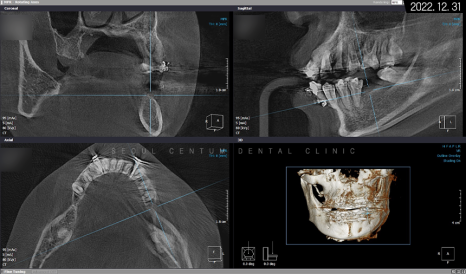

따라서 적정 시기에

CT를 촬영해 치조골 폭과 밀도를

철저하게 분석한 다음 정확한 자리를 선정하고

임플란트 식립을 진행했습니다.